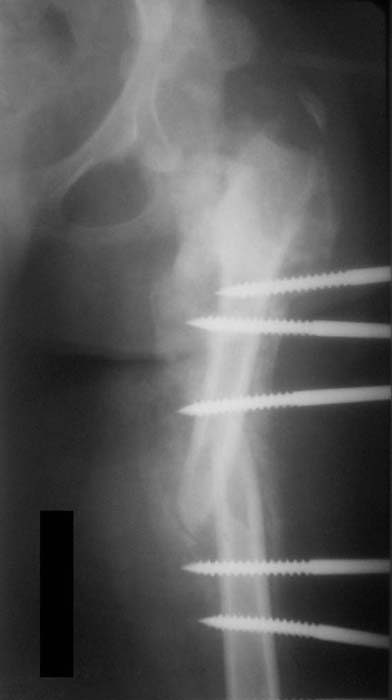

Хотелось бы увидеть рану с разных ракурсов и рентгенограммы таза и бедра. Тогда можно создать представление о площади и глубине раны.

Можно наложить простейший аппарат таз-бедро и подвесить больного (он с ним и ходить сможет), а потом спокойно перемещать лоскуты.

Такая мысль тоже приходила. Не решились, так как:1.Выраженный остеопороз костей таза и бедра, больная тучная - высок риск того, что стержни не выдержат. 2.Сейчас больная передвигается в инвалидном кресле - хоть какая-никакая, а динамизация. Если лишить её этой возможности - застойная пневмония со всеми вытекающими...